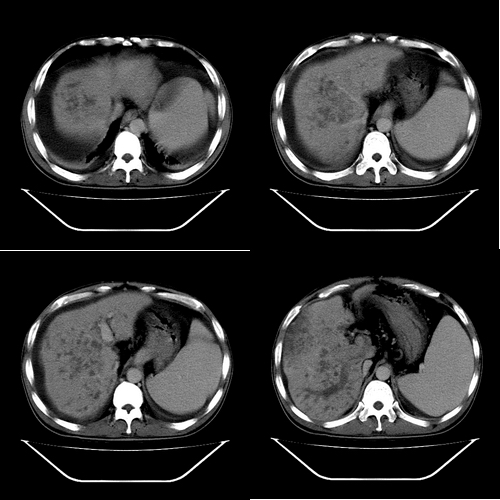

以下是引用yz在2006-6-2 12:20:00的发言:[br]肝左右叶比例失调,左叶体积明显缩小,肝边缘凹凸不平呈波浪状外观,肝左右叶可见不规则之斑片状低密度影,边界不清,以右叶为甚,肝门区增宽,增强后于动脉期病灶不均匀强化,门脉及延迟期均呈低密度,门脉主干及其右支无强化,以门脉右支明显,其内可见低密度影充填,门脉主干周围可见强化的细小侧支循环血管影。脾大,脾门血管明显增粗,脾后左侧膈脚前可见串珠状增粗强化血管影,并见胸腹水征。[br]1、考虑为弥漫性肝癌并肝门静脉主干及其右支癌栓形成,门脉海绵化。[br]2、肝硬化,脾大并门脉高压。[br]3、双侧少量胸水、腹水。